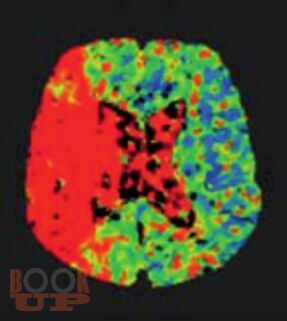

Руководство стандартизирует подходы к диагностике, лечению, реабилитации и вторичной профилактике ишемического инсульта. Изложение построено в соответствии с реальной логикой ведения пациента: от дефиниций и дифференциальной диагностики с имитаторами, через патогенетические подтипы, экстренную нейровизуализацию, реперфузионную и базисную терапию, раннюю реабилитацию, до поиска причины инсульта и вторичной профилактики.

Материал представлен в компактной форме с использованием схем, таблиц, алгоритмов и клинических примеров. Отдельные разделы посвящены инсульту у беременных и церебральному венозному тромбозу.